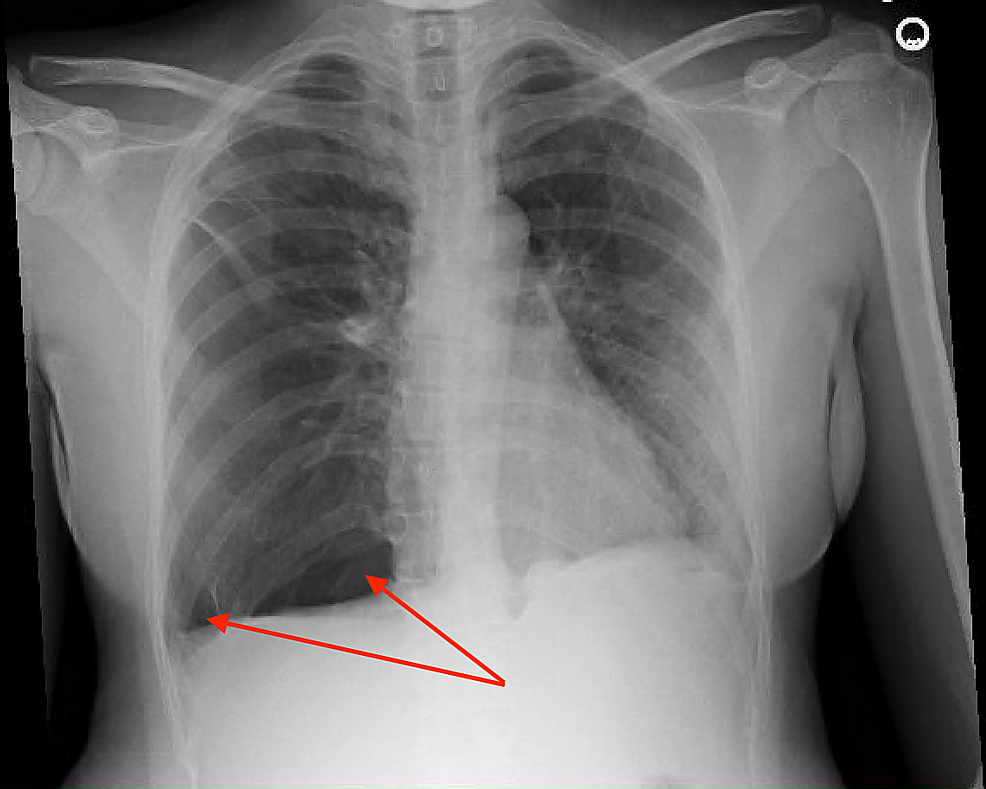

What Is A Small Pneumothorax . A pneumothorax is a collapsed lung. A pneumothorax is when air gets inside your chest cavity and creates pressure against your lung, causing it to collapse. A pneumothorax is a collection of free air in the chest outside the lung that causes the lung to collapse. A pneumothorax is described as spontaneous. A pneumothorax is an accumulation of air or gas in the space between the lung and the chest wall that occurs when a hole develops in the lung that allows air to escape. Pneumothorax occurs when air gains access to, and accumulates in, the pleural space. In some cases, a computerized tomography (ct) scan may be. This is the space between the outside of your lung and your ribcage. A pneumothorax is a collection of air inside the pleural space, which is the space between the lungs and chest wall (figure 1). A pneumothorax happens when air leaks into the pleural cavity.

A pneumothorax is a collection of air inside the pleural space, which is the space between the lungs and chest wall (figure 1). In some cases, a computerized tomography (ct) scan may be. A pneumothorax happens when air leaks into the pleural cavity. A pneumothorax is a collapsed lung. This is the space between the outside of your lung and your ribcage. A pneumothorax is an accumulation of air or gas in the space between the lung and the chest wall that occurs when a hole develops in the lung that allows air to escape. A pneumothorax is a collection of free air in the chest outside the lung that causes the lung to collapse. Pneumothorax occurs when air gains access to, and accumulates in, the pleural space. A pneumothorax is described as spontaneous. A pneumothorax is when air gets inside your chest cavity and creates pressure against your lung, causing it to collapse.